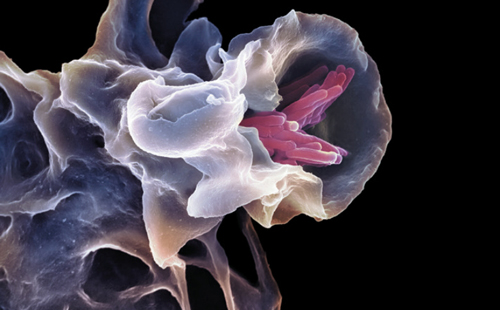

结核分枝杆菌是一种细胞内的病原体。并在免疫细胞称为巨噬细胞中感染、持续存在和复制。下图就是吞噬结核分枝杆菌(粉色)的巨噬细胞。这些细胞对于细菌来说是一个不易生长的环境:吞噬细菌到膜结构称为吞噬体的过程触发一系列事件,在另一个细胞器,溶酶体中水解酶分解定向目标,破坏病原体。但结核杆菌为了生存已经进化出通过防止被吞噬体酸化以及吞噬体和溶酶体融合,在这种吞噬中幸存下来的机制。